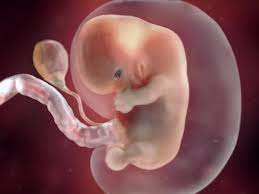

Após 8 semanas já tem braços e pernas aparentes e começa a formação dos dedos. Isso significa que ele é um pouco menos que um grão de feijão. Às vezes a medida é feita da cabeça ao osso sacro e outras vezes da cabeça aos pés.

Os pulsos do bebê estão flexionados e as mãos estão juntas sobre o peito. O fato é que às vezes o desenvolvimento e o crescimento de um embrião humano ocorrem espasmodicamente. Às 8 semanas de gravidez o seu bebé tem o tamanho de um feijão vermelhoCom 8 semanas de gravidez o bebé mede entre 14 a 20 mm medida da cabeça à anca e pesa cerca de 1 g.

Os pulsos do bebê estão flexionados e as mãos estão juntas sobre o peito. Apesar de ainda ser minúsculo já apresenta transformações e já pode ser chamado de feto agora. Desenvolvimento do seu bebê. Semana 8 da gravidez O bebê mede 20 mm. Isso significa que ele é um pouco menos que um grão de feijão. Com 4 semanas o bebê tem o tamanho de um grão de arroz e o seu coração já começa a bater. Seu útero está crescendo para acomodar o novo hóspede que agora mede em torno de 19 centímetro. Agora ele já mede cerca de 16 cm e é do tamanho de um grão de feijão jalo. Com 8 semanas de gestação o esqueleto do.